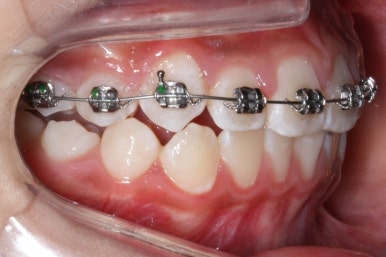

첫 장치 부착한 모습입니다.

아직 유치가 몇 개 남아있기에 장치가 전체적으로 부착되지 않습니다. 우선 앞니 4개만 먼저 치열을 맞추고 위쪽 어금니는 후방 이동을 해주면서 교합을 맞추며 덧니가 내려올 공간을 확보합니다.

연산동덧니교정 키다리아저씨치과에서는 메탈 장치를 사용했습니다.

많이 사용 되는 클리피씨 장치 등의 세라믹 보다는 아이가 양치하기 쉬운 부피가 작고 비용도 덤으로 낮은 메탈장치를 사용했습니다.